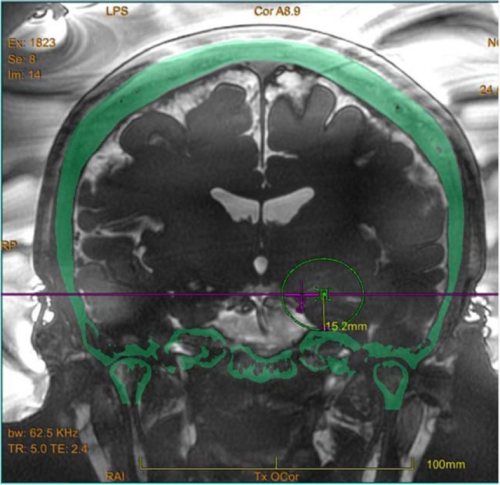

脑海绵状血管瘤(CCMs)是一种低流量血管畸形;影像学研究估计其患病率为0.4%至0.8%。47%的病例通过影像学确诊,25%的病例通过惊厥确诊,12%的病例通过脑出...